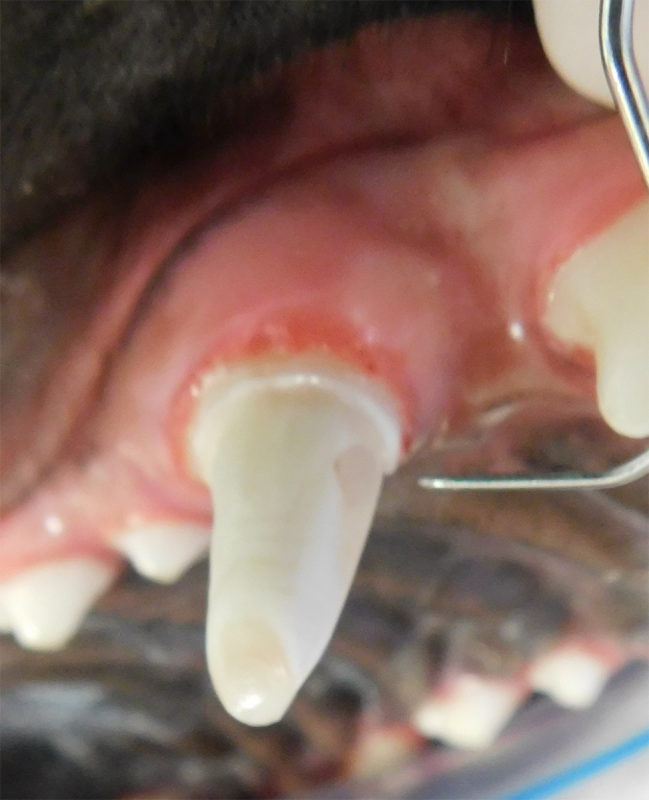

Tooth resorption is a disease process where the body begins to break down the adult tooth. It is widely known to occur in cats but can also occur in dogs. In cats these lesions are thought to be inflammatory, while in dogs they can be more of a replacement resorption process. These lesions can be very painful and should be treated, generally with extraction depending on the type of resorption that is occurring. The disease can be progressive and affect many teeth over several years. It is important to have regular checkups and yearly dental cleanings to monitor for these lesions.